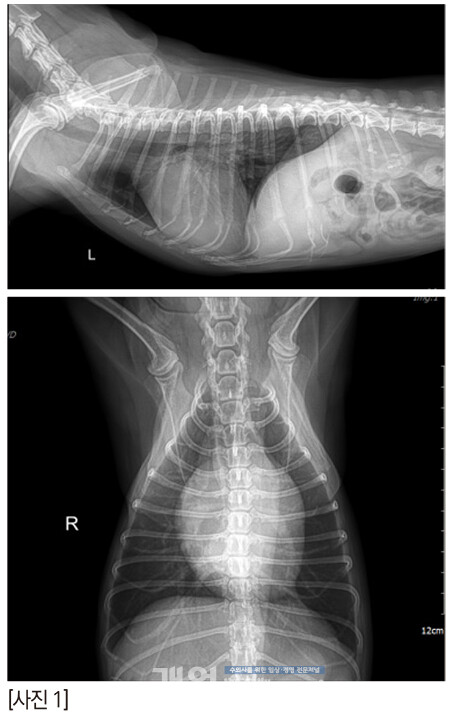

그래서 TEE 를봤다.

zone 2의 스틸컷이다. 어때 보이는가? 잘 닫히고 괜찮은가?

anterior leaflet의 끝단이 flail 되고 있다. 늘상 만나는 심각한 수준의 아이들 보다는 좀 낫긴 한데, 퇴행성 변화로 판막의 끝단이 너덜거리고, anterior leaflet의 건삭은 조금씩 닳아서 끊어지고 있나보다. 끝단이 좌심방을 향해 있다.

anterior의 zone 2-3과 posterior의 zone 2가 좀 뒤집어지고 있다. 이것은 건삭의 일부가 끊어져 너덜거리는 것으로 예측한다. 2D에서는 역류가 심해 보이지 않았지만 3D에서는 꽤 심해 보인다.